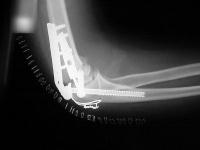

Initial fixation:

Films on arrival, one week after surgery. Neurovascular exam is normal. Early loss of fixation.

Finally, the titanium olecranon screw was replaced with a longer 6.5 mm stainless screw and tension band wire. Following this, the elbow was stabilized with an EBI hinged external fixator (not shown), planning to leave this on four weeks, anticipating inadvertent weight bearing due to the patient's bilateral calcaneal fractures.